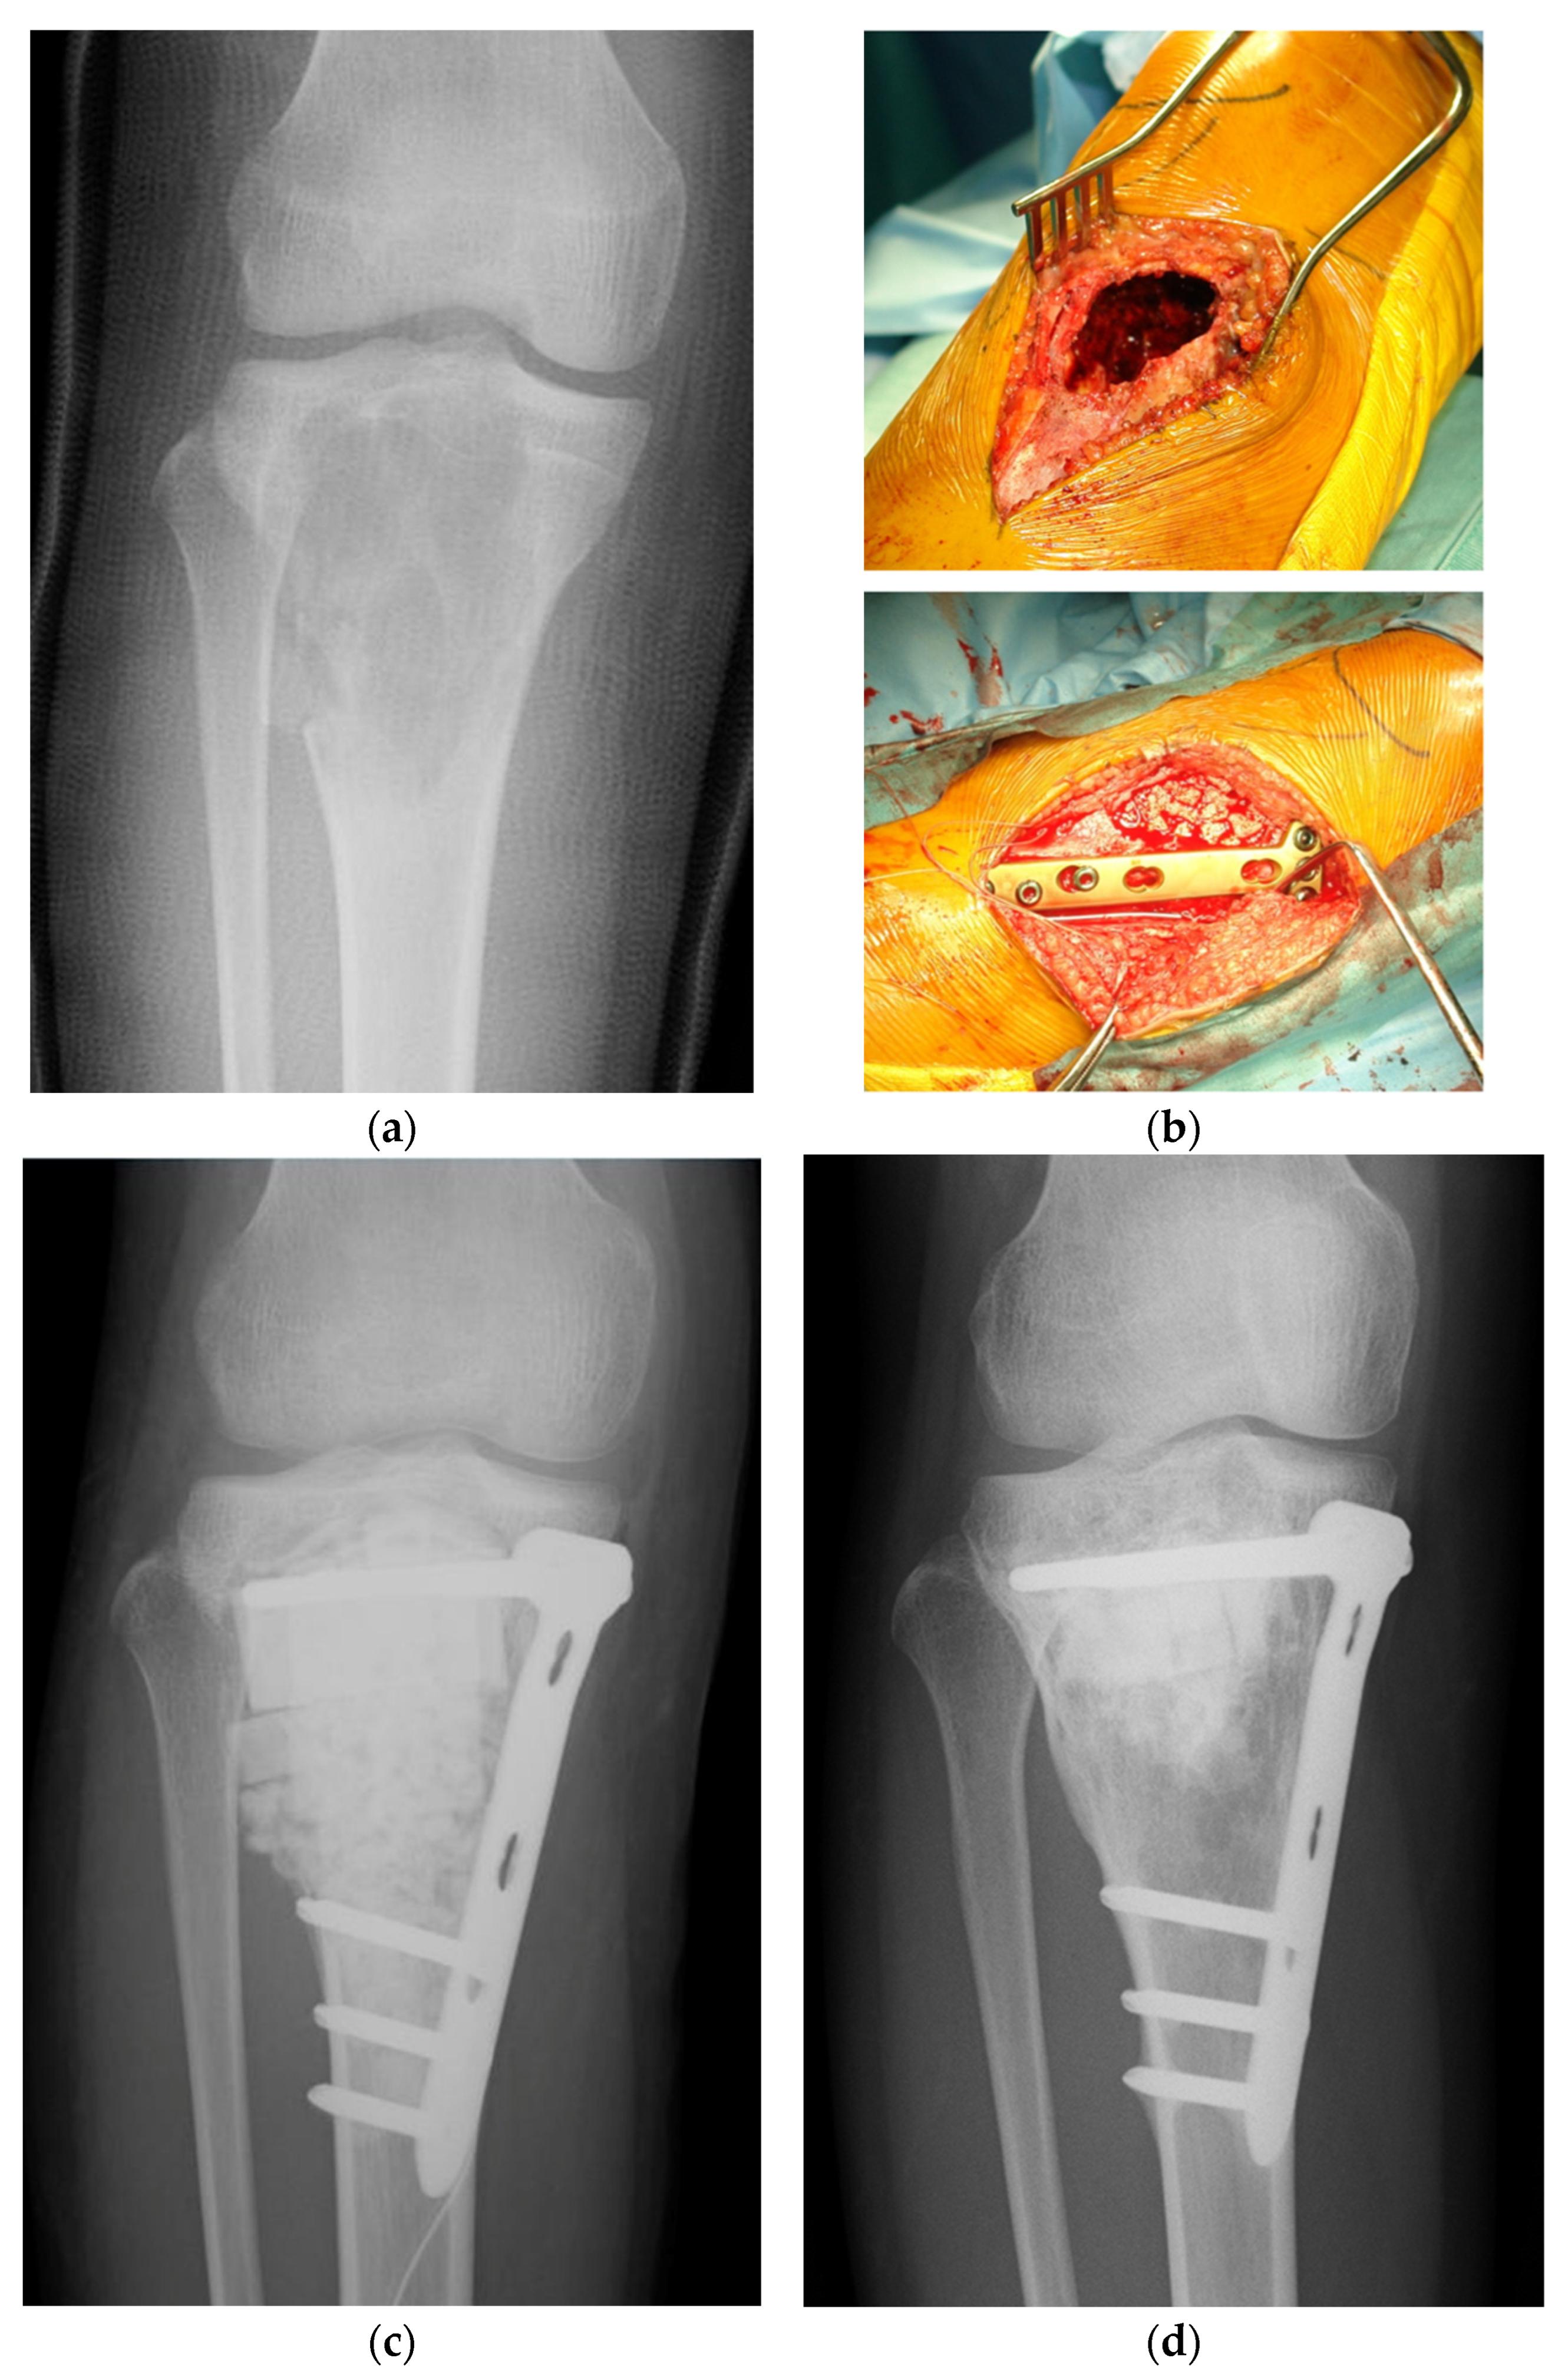

- Tanaka, T.; Kumagae, Y.; Saito, M.; Chazono, M.; Komaki, H.; Kikuchi, T.; Kitasato, S.; Marumo, K. Bone formation and resorption in patients after implantation of beta-tricalcium phosphate blocks with 60% and 75% porosity in opening-wedge high tibial osteotomy. J. Biomed. Mater. Res. B Appl. Biomater. 2008, 86, 453–459. [Google Scholar] [CrossRef]